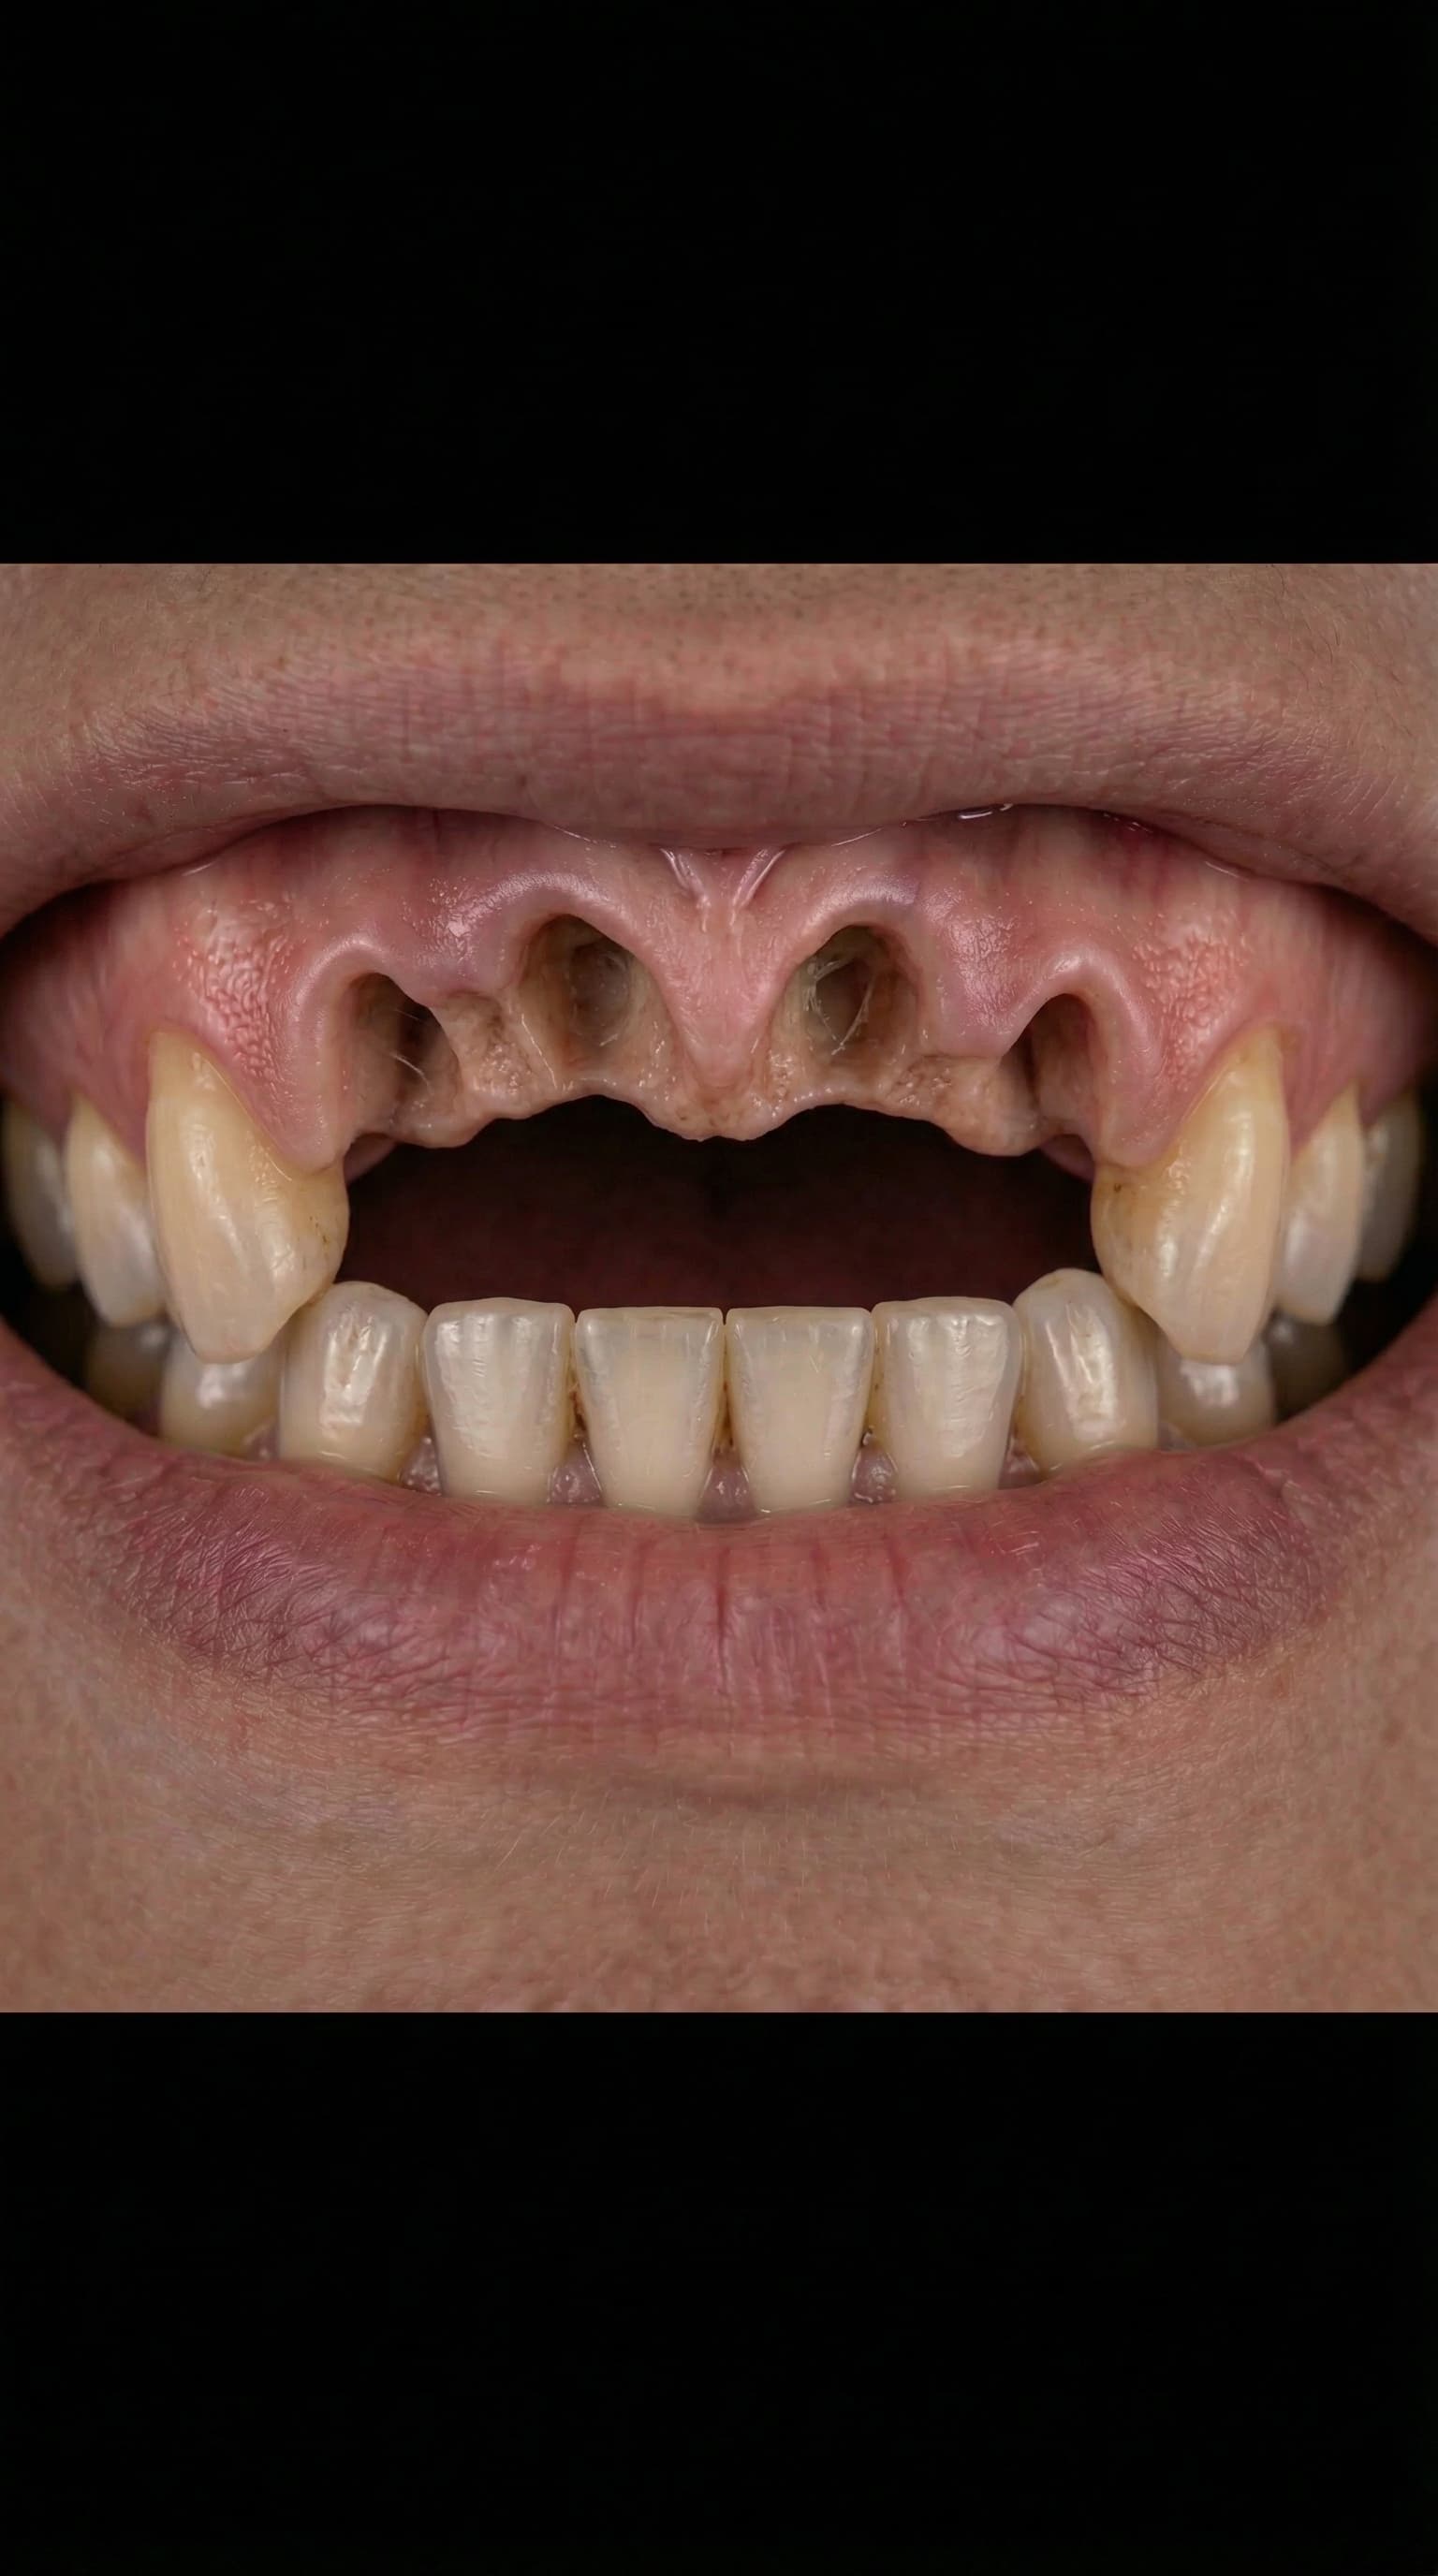

Full Arch Transformation

Watch a complete All-on-4 dental implant journey — from damaged teeth to a brand new smile. Every step performed by Dr. Antipov at our Roseville office.

Severely worn and damaged upper teeth — patient unable to eat or smile comfortably